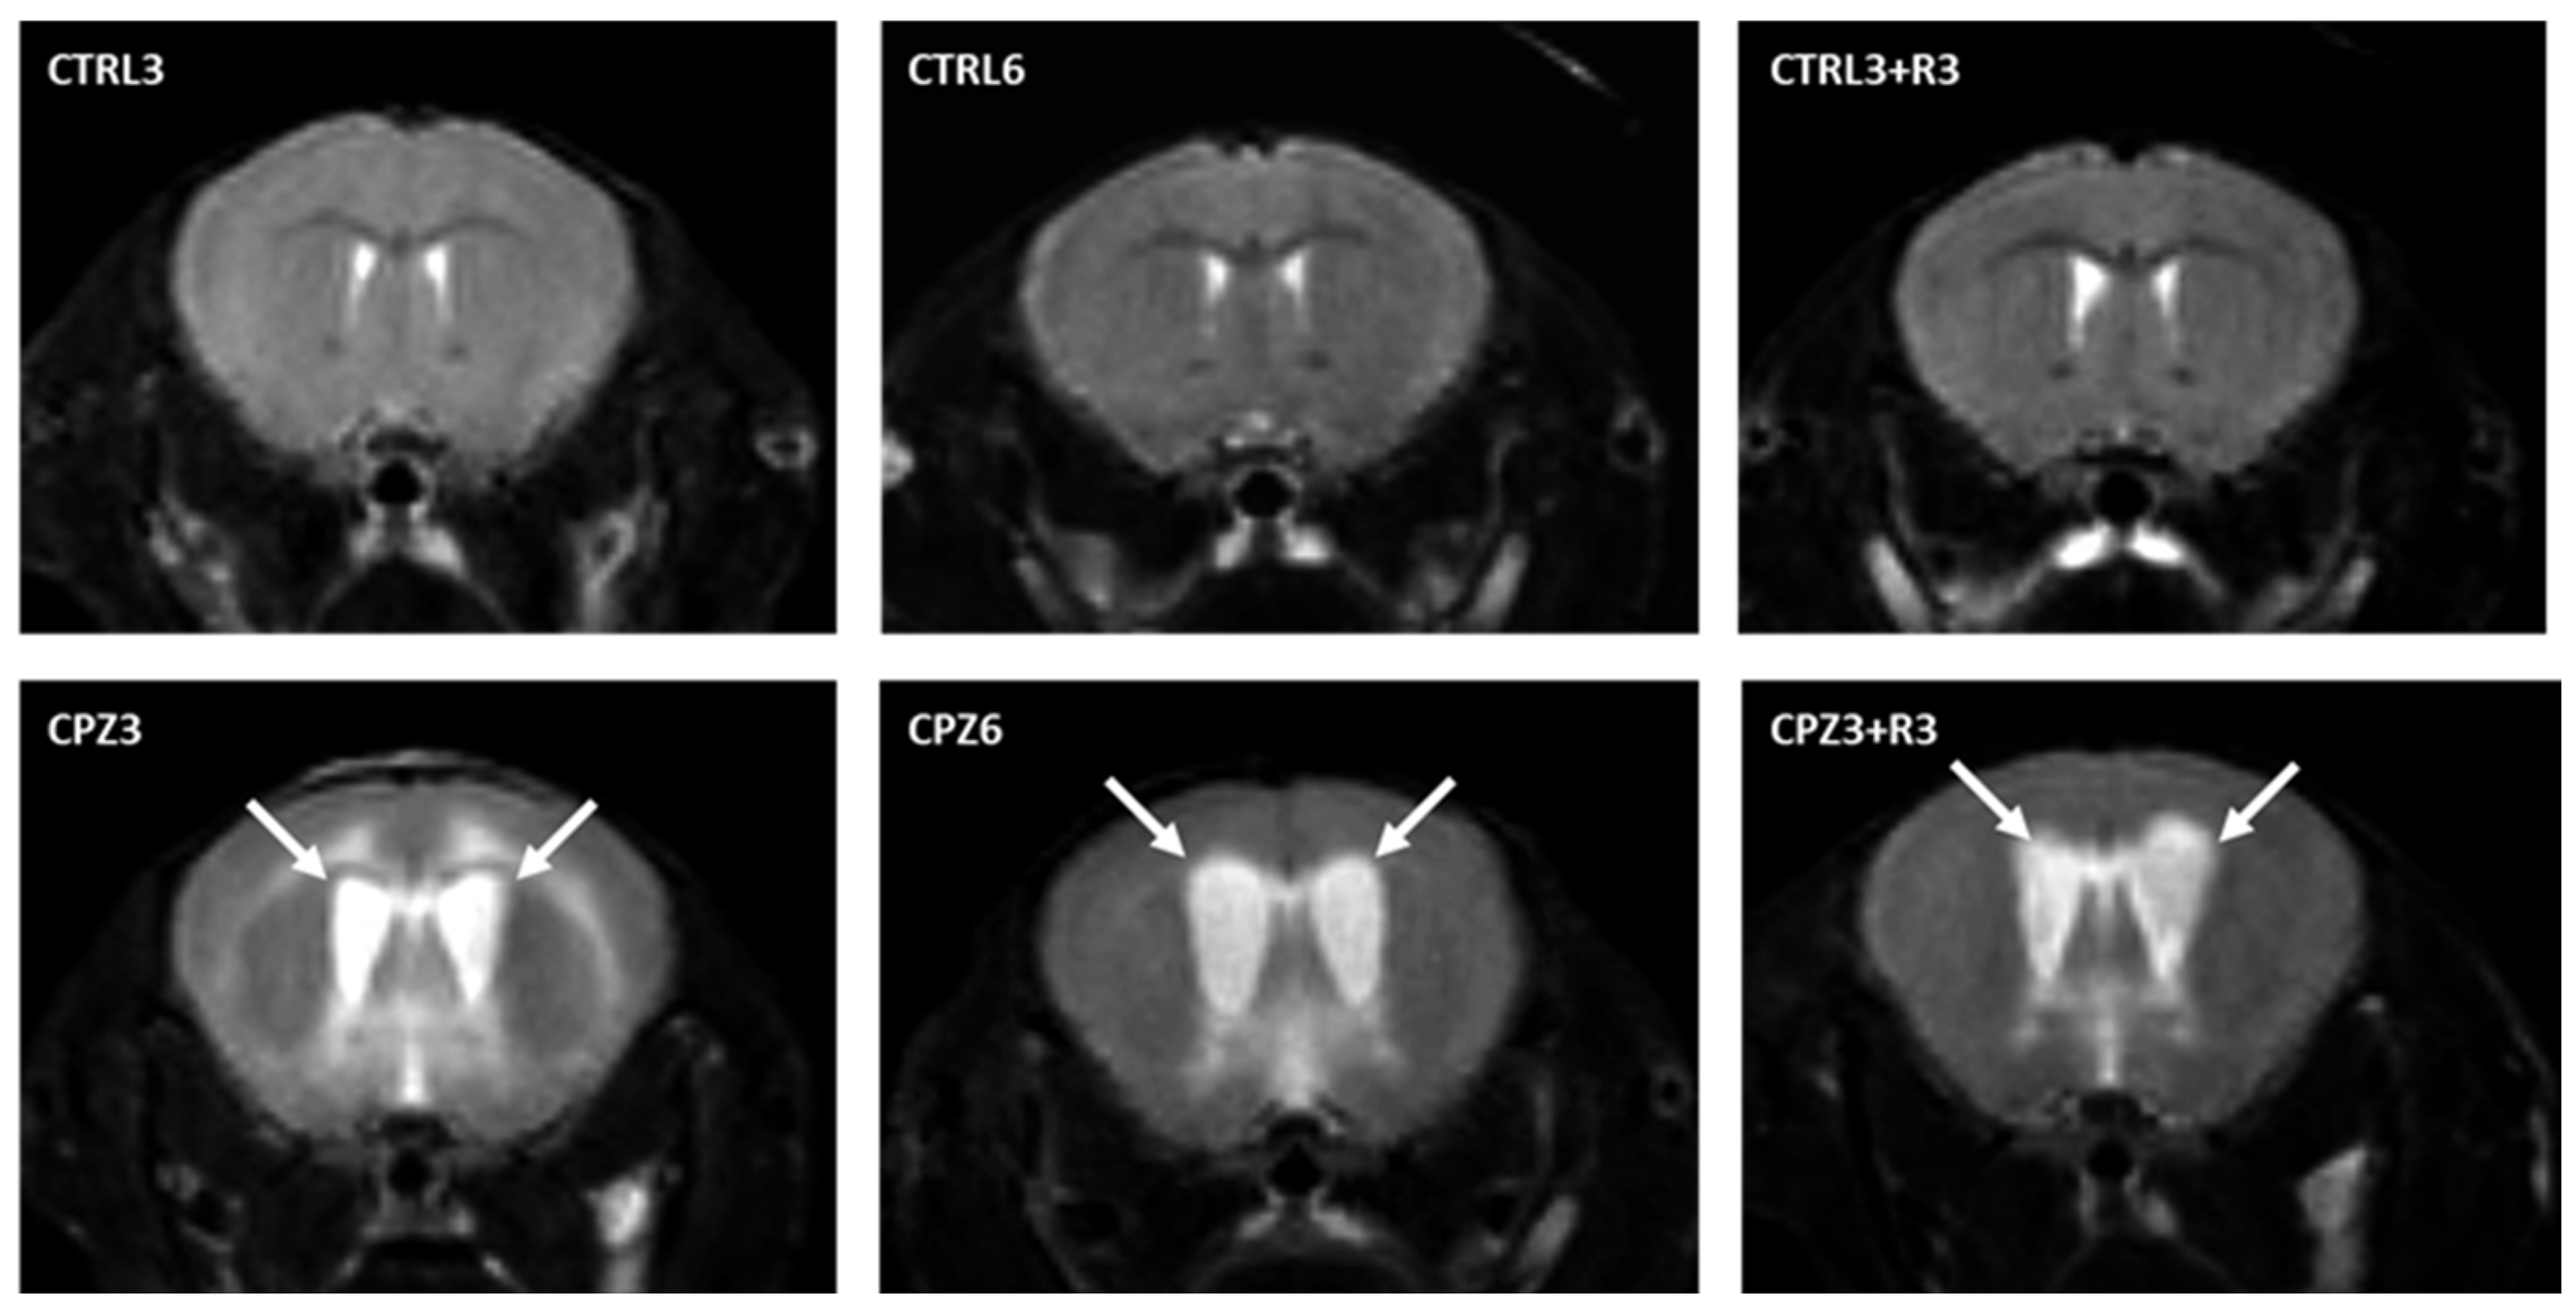

First and to investigate the effects of CPZ on the mouse brain, densitometric analyses of magnetic resonance imaging (MRI) were performed at the beginning and end of the treatment. T2-weighted MRI images were used to study the degree of demyelination but also allowed the detection of hydrocephalus in CPZ-treated mice (Figure 1). On one hand, hyperintense areas observed in the images, along with brain flattening, suggested a higher water content in the parenchyma. An increased intensity was noted at the level of the ventricles and in the surrounding nervous tissue in mice treated with CPZ for 3 weeks (CPZ3) compared to controls, regardless of recovery time (Figure 1; arrows). However, this finding was more pronounced in mice treated with CPZ for 6 weeks (CPZ6). On the other hand, the hydrocephalus was further demonstrated using the Evans index, calculated as the ratio of brain diameter to inter-ventricular distance. In fact, CPZ6 mice and those treated with CPZ for 3 weeks followed by a 3-week recovery period (CPZ3+R3) showed Evans ratios above 0.3, significantly higher than their respective controls (Figure 2).

Figure 1.

T2-weighted coronal magnetic resonance images at the level of the anterior commissure from mouse brains: control, treated with cuprizone for 3 weeks (CPZ3), 6 weeks (CPZ6), and 3 weeks followed by a 3-week recovery period (CPZ3+R3). Arrows indicate hyperintense areas.